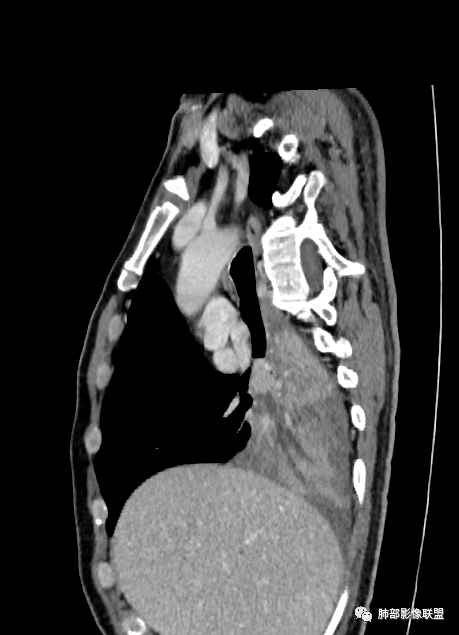

病灶主要在后、外基底段

长轴、支气管、血管是观察的重点

这就需要重建

中间段支气管

基底干是外侧朝腔内压迫?还是外侧壁占位突入腔内?

这是肺门淋巴结压迫、侵犯支气管导致堵塞?还是腔内本身肿瘤?

远端支气管是粘液栓

首先血管未见明显侵犯、移位,提示病灶:炎性;肿瘤:外朝内——含粘液类腺癌(肺门淋巴结转移),腔内肿瘤(鳞癌、腺癌、类癌、小细胞、粘液表皮等)

腔内肿瘤,远端堵塞

这是源头

这些如果单纯不张肯定强化明显